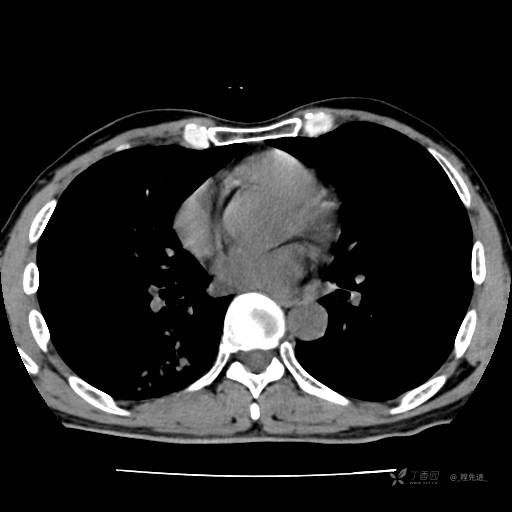

2月特别精彩病例|咳嗽、咳痰20余天,典型病例分享【结果已公布】

患者年龄:51岁

主诉:咳嗽、咳痰20余天

简要病史:20余天前开始出现咳嗽、咳痰症状,阵发性刺激性咳,白色粘痰,不易咳出,无发热,无咯血,无恶心、呕吐等不适,未诊治,咳嗽、咳痰症状持续存在。

体格检查:T:36.3 ℃ P:79 次/分 R:20 次/分 BP:128/64 mmHg,神志清楚,呼吸平稳,双肺呼吸音粗,右下肺闻及细湿性啰音。心率79次/分,节律整齐,各瓣膜听诊区未闻及病理性杂音。腹部未见异常,双下肢无水肿。

辅助检查:我院门诊胸部CT示:如下。心电图:窦性心律;正常心电图。